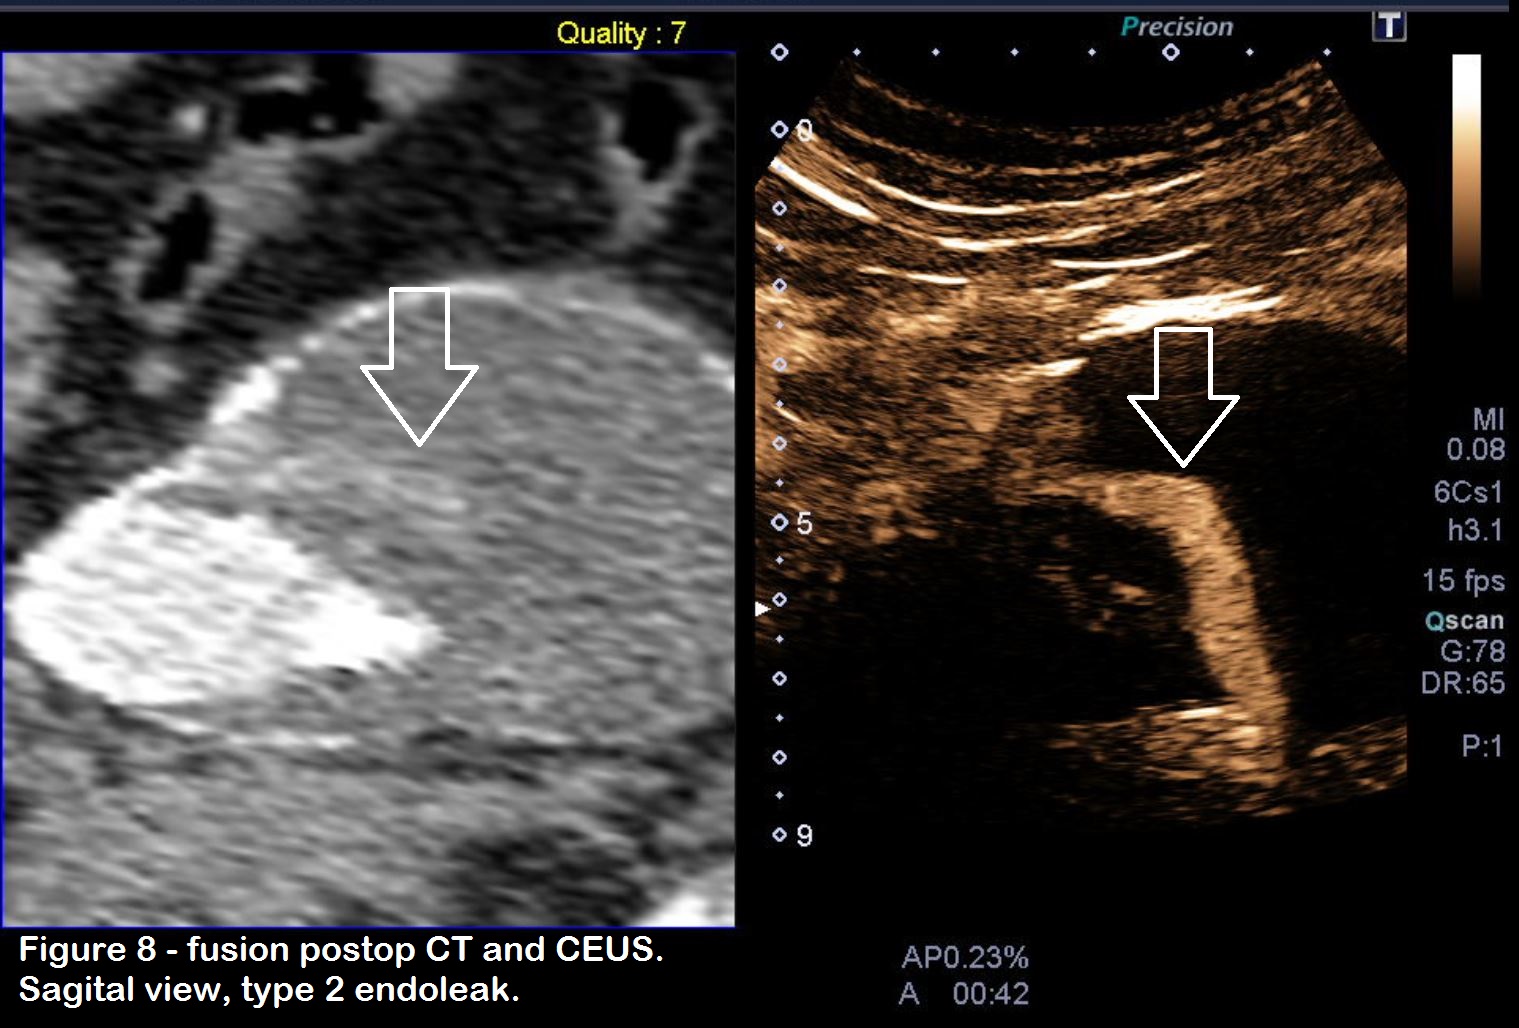

Figure 8: US/CT fusion also provides a better understanding of the anatomy, which can be very challenging at times. In this case, the type 2 endoleak extends a long distance throughout the sac.